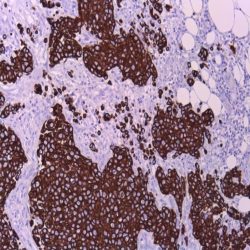

آنتی بادی CD34 برند NOVOCELL یک آنتی‌ بادی تک‌ زنجیره‌ای مونوکلونال است که با اتصال اختصاصی به آنتی‌ ژن سطحی CD34، امکان شناسایی و جداسازی سلول‌ های بنیادی خونساز را فراهم می‌ کند. این آنتی‌ بادی برای تکنیک‌ های ایمونوفلوئورسانس و فلوسایتومتری بهینه‌ سازی شده و با ایجاد سیگنال فلورسنت قوی و اختصاصی، امکان تشخیص دقیق سلول‌های CD34+ را در نمونه‌ های خون محیطی و مغز استخوان میسر می‌ سازد. شرایط نگهداری این محصول در دمای ۲ تا ۸ درجه سانتی‌ گراد و دور از نور مستقیم خورشید تعریف شده و پس از باز شدن ویال، حداکثر تا یک ماه قابلیت استفاده دارد.

کاربردهای آنتی بادی CD34 برند NOVOCELL

Novocell CD34 antibody enables precise identification and quantification of hematopoietic stem cells in flow cytometry analysis.

This monoclonal antibody is essential for bone marrow transplantation monitoring and leukemia immunophenotyping studies.